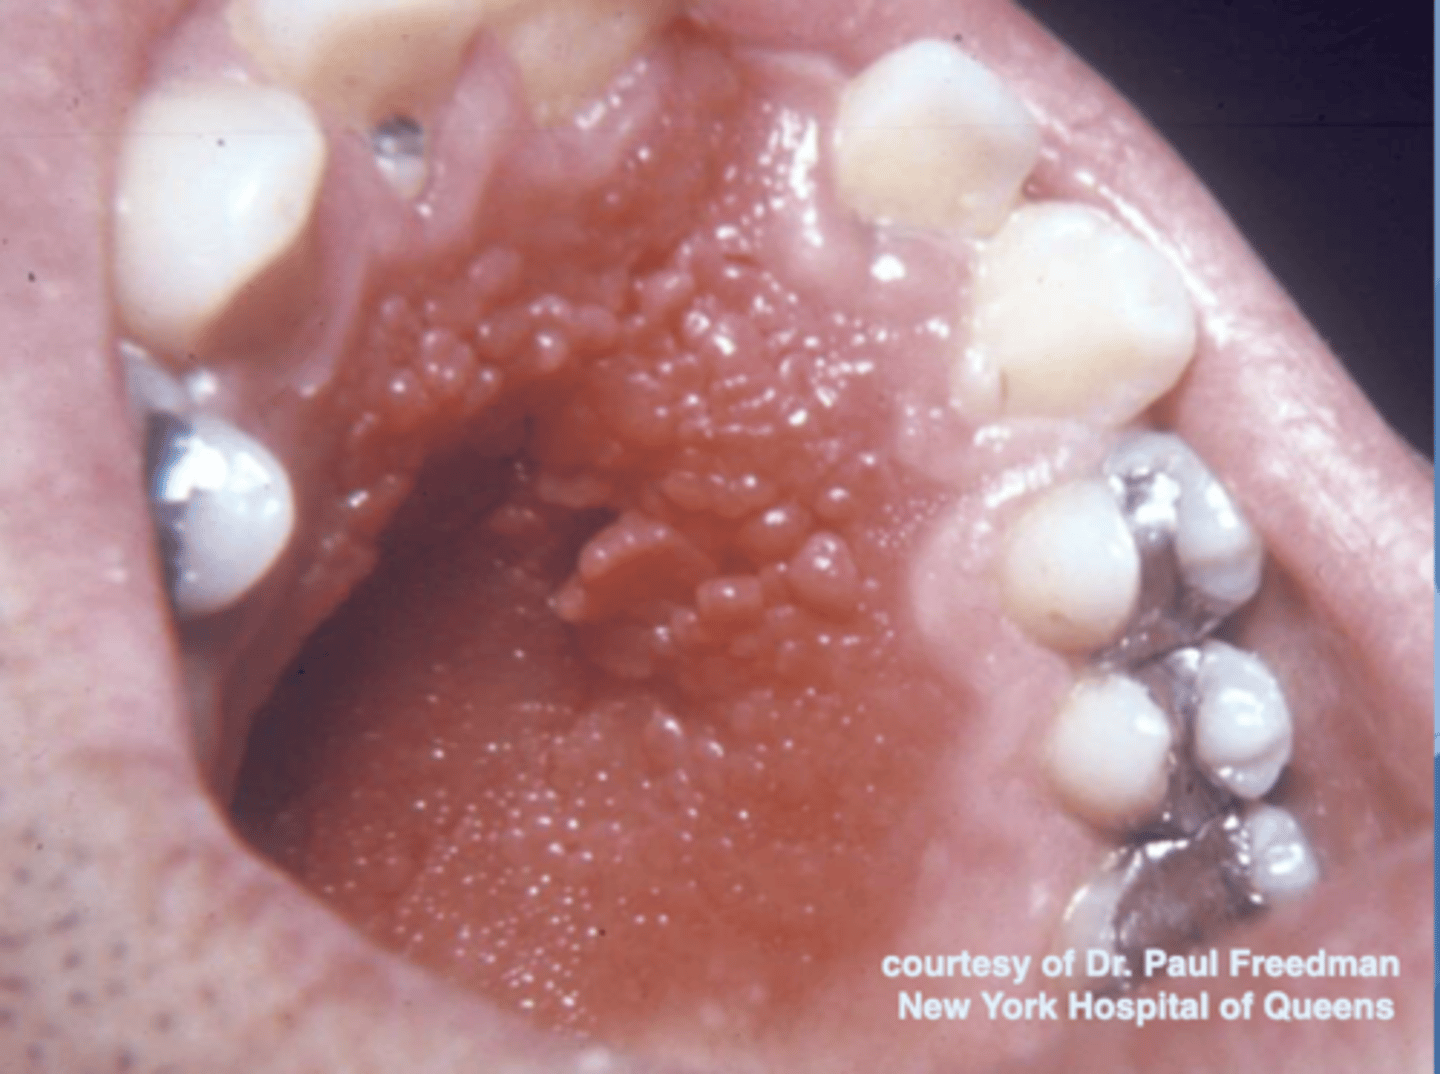

what do you suspect?

inflammatory papillary hyperplasia w/ secondary candidal infection

*can tell pt also has candidiasis b/c of erythema

what are these clinical features of?

-hard palate beneath denture base

-pink or pebbly mucosa

-erythema --> suggests secondary candidal infection

inflammatory papillary hyperplasia

how is inflammatory papillary hyperplasia treated? (3)

-mild cases --> resolved w/ removal of denture

-established cases --> excision of hyperplastic tissue + relining/refabrication of denture

-antifungal therapy if needed